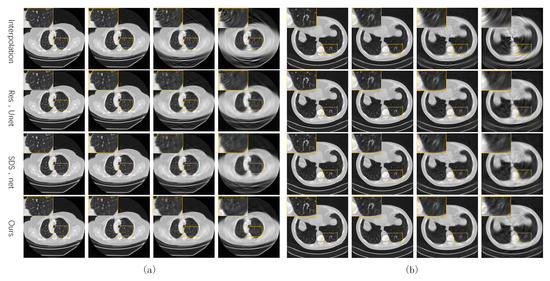

3.2.1. Training with the Sinogram Domain Loss

Figure 4 shows some test CT slices reconstructed by the four methods on the two datasets. The reconstructed images of the three machine-learning-based models are close and significantly better than those of linear interpolation. As the sparsity level s increases, the quality of all reconstructed CT images decreases significantly, and the linear interpolation method degrades the most significantly due to not using prior knowledge in the training set. Our network performs slightly better than the two baseline networks (SDS-net and Res-Unet) at higher sparse levels (). As shown in the local zooms corresponding to and 15, the proposed network is better in terms of edge preservation of CT images.

Figure 4.

Reconstructed CT images of the four methods from our own dataset (a) and the AAPM dataset (b).